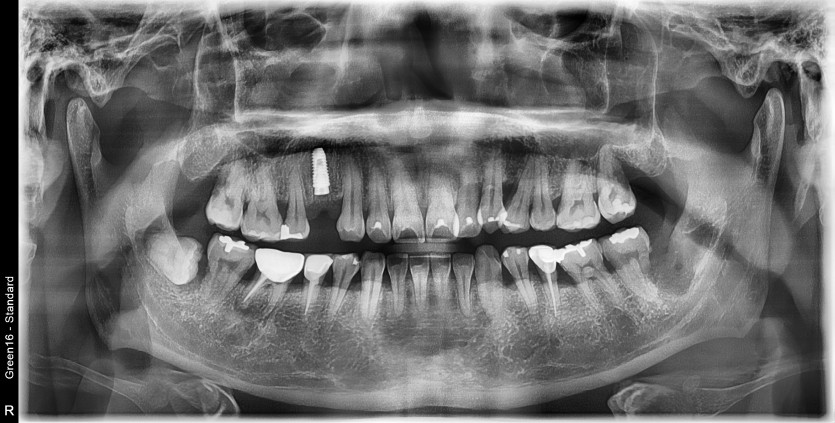

#38 사랑니 발치

구강외과 전문의가 발치했습니다.